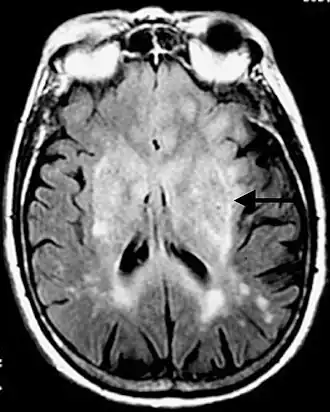

- Standardverfahren ist die Magnetresonanztomographie (MRT), auch Kernspintomographie genannt, ein diagnostisches Schnittbildverfahren zur Darstellung von Organen und Geweben mit Hilfe von Magnetfeldern. Sie basiert auf der Gewebestruktur und dem Wassergehalt und hat eine sehr hohe Erkennungsrate für Hirntumoren, ohne ionisierende Strahlung einzusetzen. Kontrastmittel ist nicht immer erforderlich. Die Magnetresonanzspektroskopie (MRS) ist ein in spezialisierten Zentren verfügbares Zusatzverfahren, um aus tumorverdächtigen Arealen ein Signalspektrum aufzunehmen und damit ihre chemische Zusammensetzung abzuschätzen.